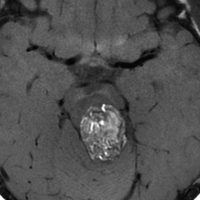

9歳男児の松果体奇形腫です。生検術と第3脳室開窓術を受けましたが,摘出術のリスクが高すぎるということで化学療法を6コース。2年間経過観察されましたが,腫瘍が増大しました。私のところへ来た時には,前後径73mmありました。

左からT2, swan, T1です。これが 類皮のう胞 dermoid cyst ということがわかります。類皮のう胞単独,あるいは成熟奇形腫の大部分としての類表皮のう胞は,かなり頻度の高いものです。松果体腫瘍で奇形腫を疑ったらまず,類皮のう胞の混在を疑います。それがあれば,かなりの確率で成熟奇形腫 mature teratomaです。

類皮のう胞は内部がほとんど皮脂,ケラチン,汗,毛髪なので,簡単に砕けるし,掻き出し吸い取ることができます。松果体成熟奇形腫の中では最も戦いやすい相手と言えるでしょう。再発しないようにするには,周囲ののう胞壁(真の腫瘍細胞)を完全摘出するしかありません。放射線も化学療法も何も効かないし,のこせば必ず再発します。

右迂回槽にちょっとdebrisは残っていますが完全摘出できました。病理は他の成分を少し混じる成熟奇形腫です。術後3年間再発はありませんし,学校へ通って体育もできています。

この手術はもちろん簡単ではありません,でもほとんどが類皮のう胞であるということがわかったので踏み込めたのです。